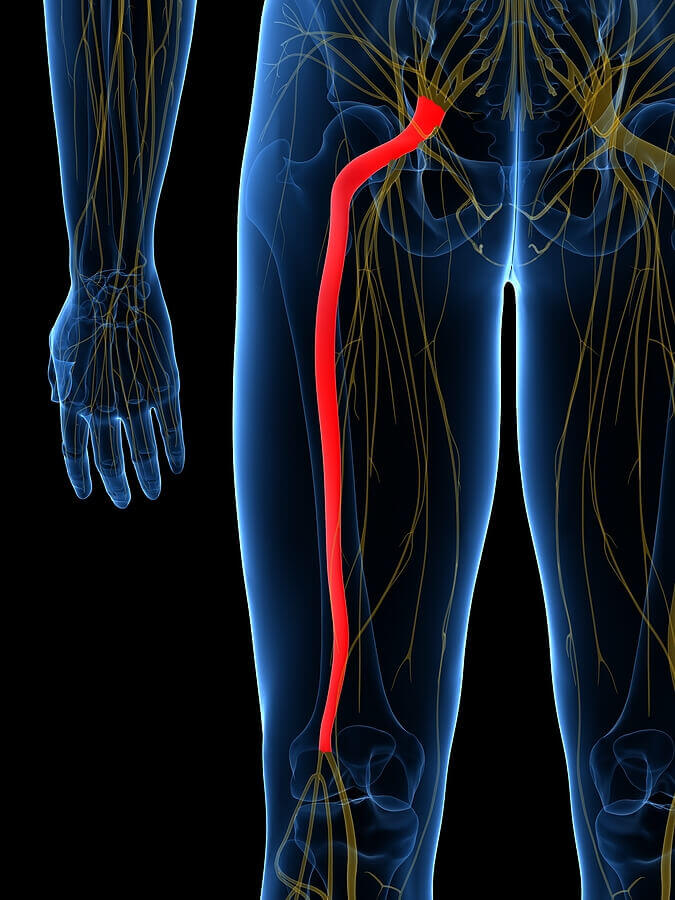

Download Sciatic nerve pain pictures